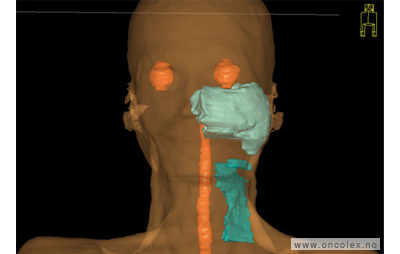

Skisse over hvordan strålefeltet planlegges:

Illustrasjon for målvolum

• GTV (Gross Tumor Volume): Identifisert tumor.

• CTV (Clinical Target Volume) GTV + omkringliggende vev hvor det kan væremikroskopisk spredning.

• ITV (Internal Target Volume): CTV + en indre margin som tar hensyn tilindre bevegelser og endringer av CTV.

• PTV (Planning Target Volume): Innstillingsmargin som inneholder ITV og samtidig tar hensyn til antatte pasientbevegelser, samt variasjoner i pasientopplegging og feltinnstillinger.

• Feltgrense. Tegnes som oftest på kroppen.